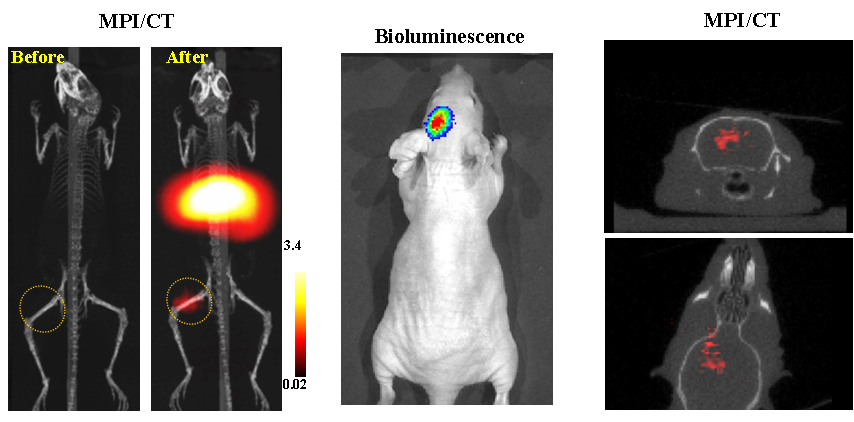

今年二月份,宋国胜教授与斯坦福大学饶江宏教授合作,通过系统的研究获得了影响磁性粒子成像信号的作用规律和关键原理,开发了新型磁性粒子探针---FeCo合金粒子,并首次应用于磁性粒子成像(MPI)。该造影剂在极低含量时(5 ng)仍具有很强的造影效果。这意味着,未来在进行人体成像时,可以使用更小剂量的造影剂,从而避免高剂量造影剂引起的肾肝损伤。基于MPI的直接成像原理,我们可以对造影剂进行正相和无背景干扰的活体成像,极大地提高信噪比。这项技术为肿瘤早期诊断、癌细胞示踪、脑中风、药物输送治疗、肺部灌注成像、胃肠出血、神经退行性疾病、磁热治疗等在活体中的可视化研究,提供了强有力的手段。相关研究成果以绿帽小说

为第一单位发表在Nature 子刊《Nature Biomedical Engineering》。该期刊是“生物医学工程”的顶级期刊。宋国胜教授为该论文的共同通讯作者。